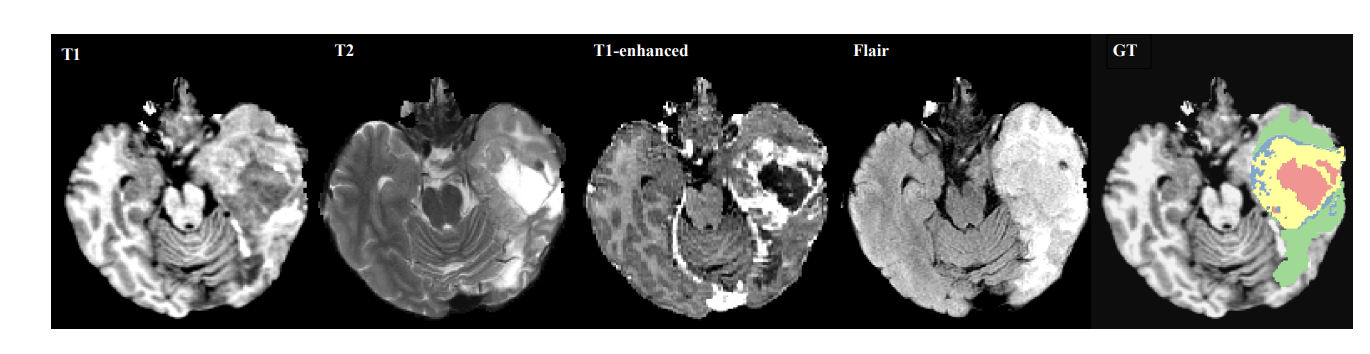

데이터셋

- 각 픽셀은 T1, T2, T1C, FLAIR과 같은 서로 다른 이미지 방식에 연결

- 각 T1, T1C, T2, FLAIR 네 가지 방식이 coregister 된 상태로 존재

- 5개의 분할 레이블(비종양, 괴사(빨강), 부종(초록) , 비대조 종양(파랑), 대조 종양(노랑))

종양영역 :

a) complete tumor region :모든 4개의 종양 구조 포함

b) core tumor region : 부종 제외한 모든 종양 구조 포함

c) enhancing tumor region : 대조된 종양 구조 포함